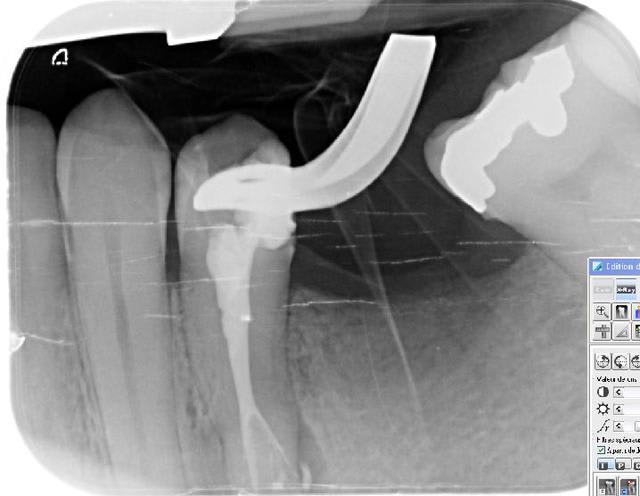

17/11/2011 à 16h13

par provoc on s'est amusé à faire une photo

pour répondre à la question avec quoi j'obture : maitre cone et condensation verticale simplement

promis je ne polluerais plus les posts d'endo

cadeau (si je puis me permettre) de fin

mon objectif avait été de dire qu'on pouvait aussi faire simple mais la critique SYSTEMATIQUE me casse les c...